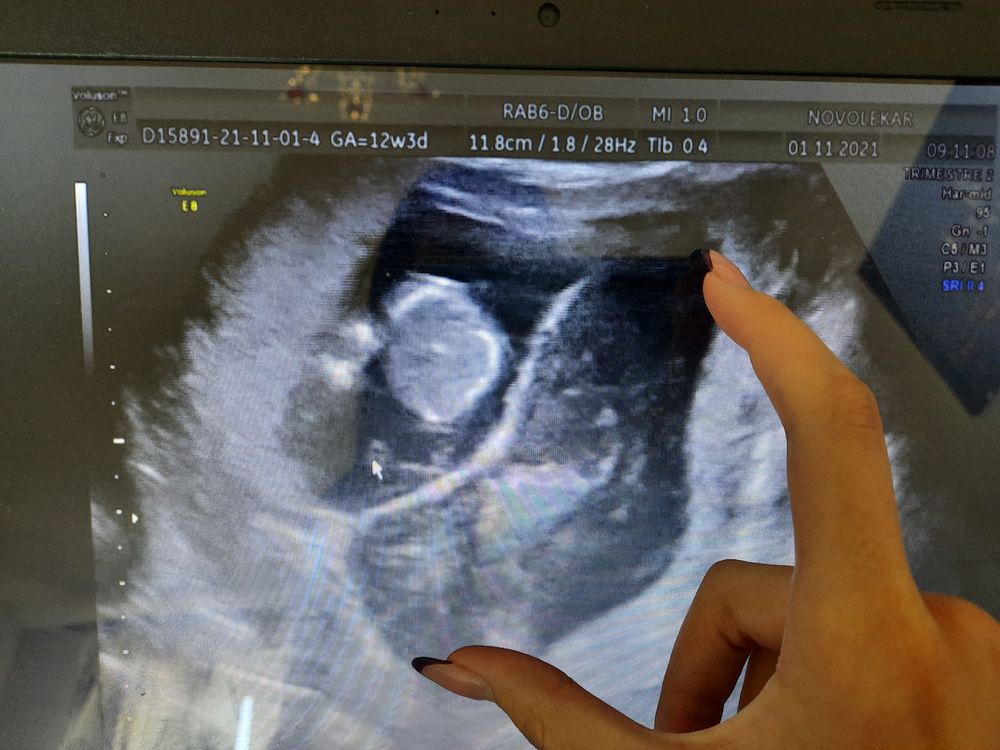

вот на фото она рядом с малышом